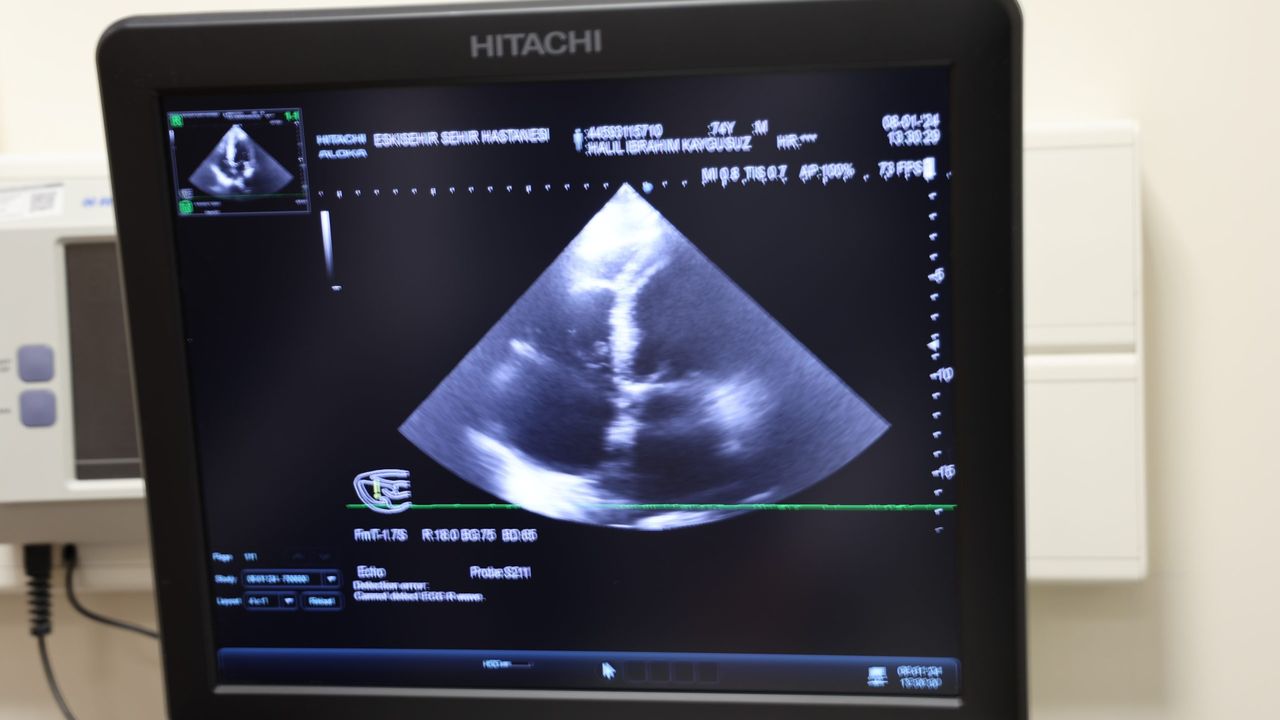

Genel olarak açık kalp ameliyatı şeklinde gerçekleştirilebilen operasyonu, hastanın kasık bölgesinden iğneyle girerek kalbinde pıhtı atan keseciğe şemsiye şeklinde parça yerleştirilmesiyle 30 dakika gibi kısa bir sürede tamamlayan Eskişehir Şehir Hastanesi doktorları, felç rahatsızlığının tekrarlanma ihtimalini en aza indirerek 84 yaşındaki Yılmaz Ünallı’yı sürekli ilaç kullanımından kurtardı. Yapılan operasyon hakkında bilgi veren Kardiyoloji Uzmanı Doç. Dr. Özge Turgay Yıldırım, “Kasıktan anjiyo gibi plastik bir iğne üzerinden ilerleyerek sol kulakçığın içine girip, oradaki keseciği bir şemsiye benzeri malzemeyle kapattık” dedi.

Birçok hastanede açık kalp ameliyatına alınan hastaların 2 ila 4 saat kadar operasyon geçirdiğini, fakat Eskişehir Şehir Hastanesi’nde bu sol atriyal apendiks kapama işlemini kesi olmadan 30 dakikalık müdahale ile tedavi ettiklerini belirten Kardiyoloji Uzmanı Doçent Dr. Özge Turgay Yıldırım, “Biz bu işlemde ritim bozukluğu olan yüksek riskli bazı hastalarda yapılan bir işlemi gerçekleştirdik. Bu işlem bölgemizde çok sık yapılan bir işlem değildir. Biz bu hastamıza ‘Sol Atriyal Apendiks Kapatma’ işlemi yaptık, tekrarlayan inmeleri olan ve mağduriyet yaşayan bir hastamızdı. Kan sulandırıcı tedavisini almasına rağmen inme tekrarlıyordu, bu yüzden bu işlemi yapmaya karar verdik. Hastamızda ritim bozukluğu var. Bu ritim bozukluğu kalbin içindeki kulakçıkta ‘apendiks’ dediğimiz bir kesecik içinde pıhtı birikmesine neden olan bir hastalık ve kalp kaynaklı inmeye neden oluyor. Biz bu kese ağzını bir şemsiye yardımıyla kapatabilirsek, bu bölgeden pıhtı atmasını ve felç geçirmesini engellemiş oluyoruz. Normalde bu işlem açık kalp ameliyatı ile de yapılabiliyor ama bizim farklı olarak yaptığımız kasıktan anjiyo gibi plastik bir iğneyle girerek ve buradan ilerleyerek, sol kulakçığın içine girip, oradaki keseciği bir şemsiye benzeri malzemeyle kapattık. Yani herhangi bir kesi olmadan kasıktan iğne yardımıyla bu işlemi yapmış olduk ve hastamızın tekrar kalp kaynaklı inme riskini çok ciddi derecede azaltmış olduk. Bu ameliyatı açık kalp ameliyatı şeklinde yaparsak önce kemiği açmamız ve kalbin içerisine girmemiz gerekiyor. Hatta kalbi kesmemiz daha sonraysa orayı kapatmamız ve bağlamamız gerekiyor ama biz bu işlemi iğneyle kasığı uyuşturarak yapıyoruz. Bu işlem yaklaşık 15 ila 30 dakika arasında sürüyor. Hastamız ise günübirlik bir yatış sonrası taburcu olabiliyor. Eğer açık kalp ameliyatı şeklinde yapılırsa hastamızın en az bir hafta yatması gerekir, onun haricinde işlem 2 - 4 saat arası sürebilir, ameliyatın içerik ve tipine göre değişir. Gerçekten pıhtı kalp içinde bu kesecikten kaynaklıysa biz zaten bu kesenin ağzını kapatıyoruz, bu durumda bu pıhtının buradan çıkıp gitmesi teorik olarak çok zor. Çok nadir olarak tekrarlayabilir tabi ama bu hastalar normalde ömür boyu kan sulandırıcı tedaviye mahkum hastalardır, biz burayı kapattığımızda kan sulandırıcıları dahi kesebiliyoruz. En önemli artısı bu ve hastamız tekrar inme geçirmiyor. Hastamız bu işlemden sonra şikayetlerinin gerilediğini, tekrar baş dönmesi ve dengesizlik şikayetlerinin olmadığını söyledi. Klinik olarak da fayda gördük” dedi.